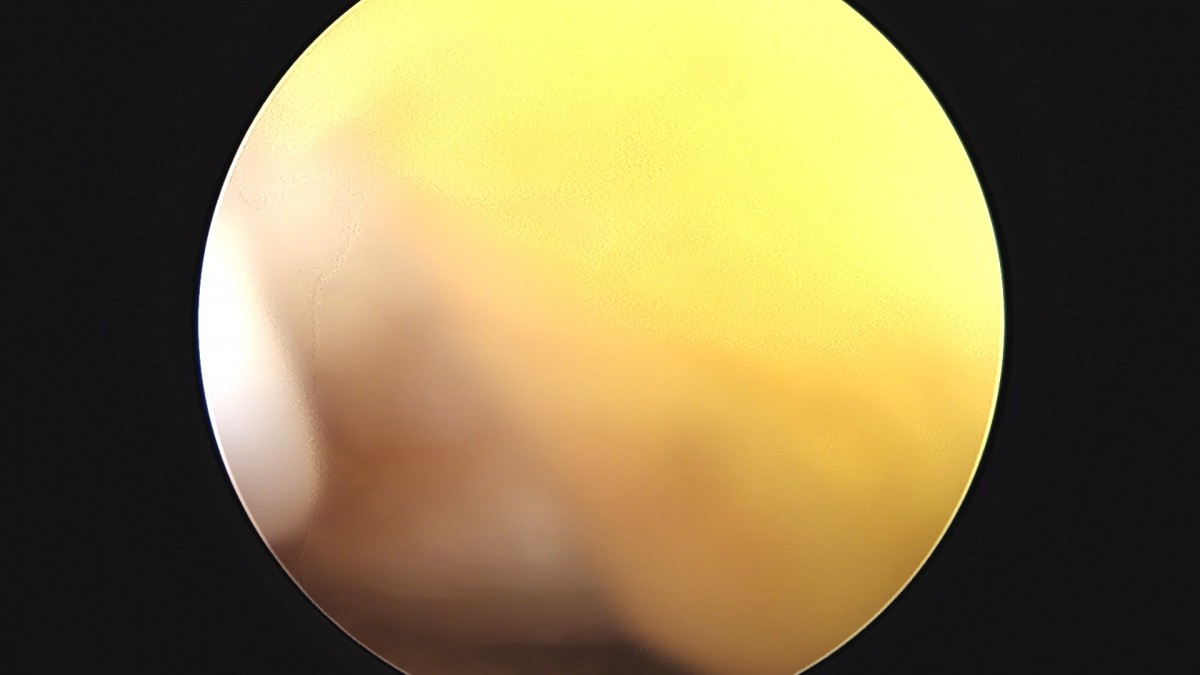

이재상원장님 무릎 반월상 연골판 절제술 강일O 환자

작성자 최고관리자 댓글 0건 조회 372회 작성일 25-09-16 16:12